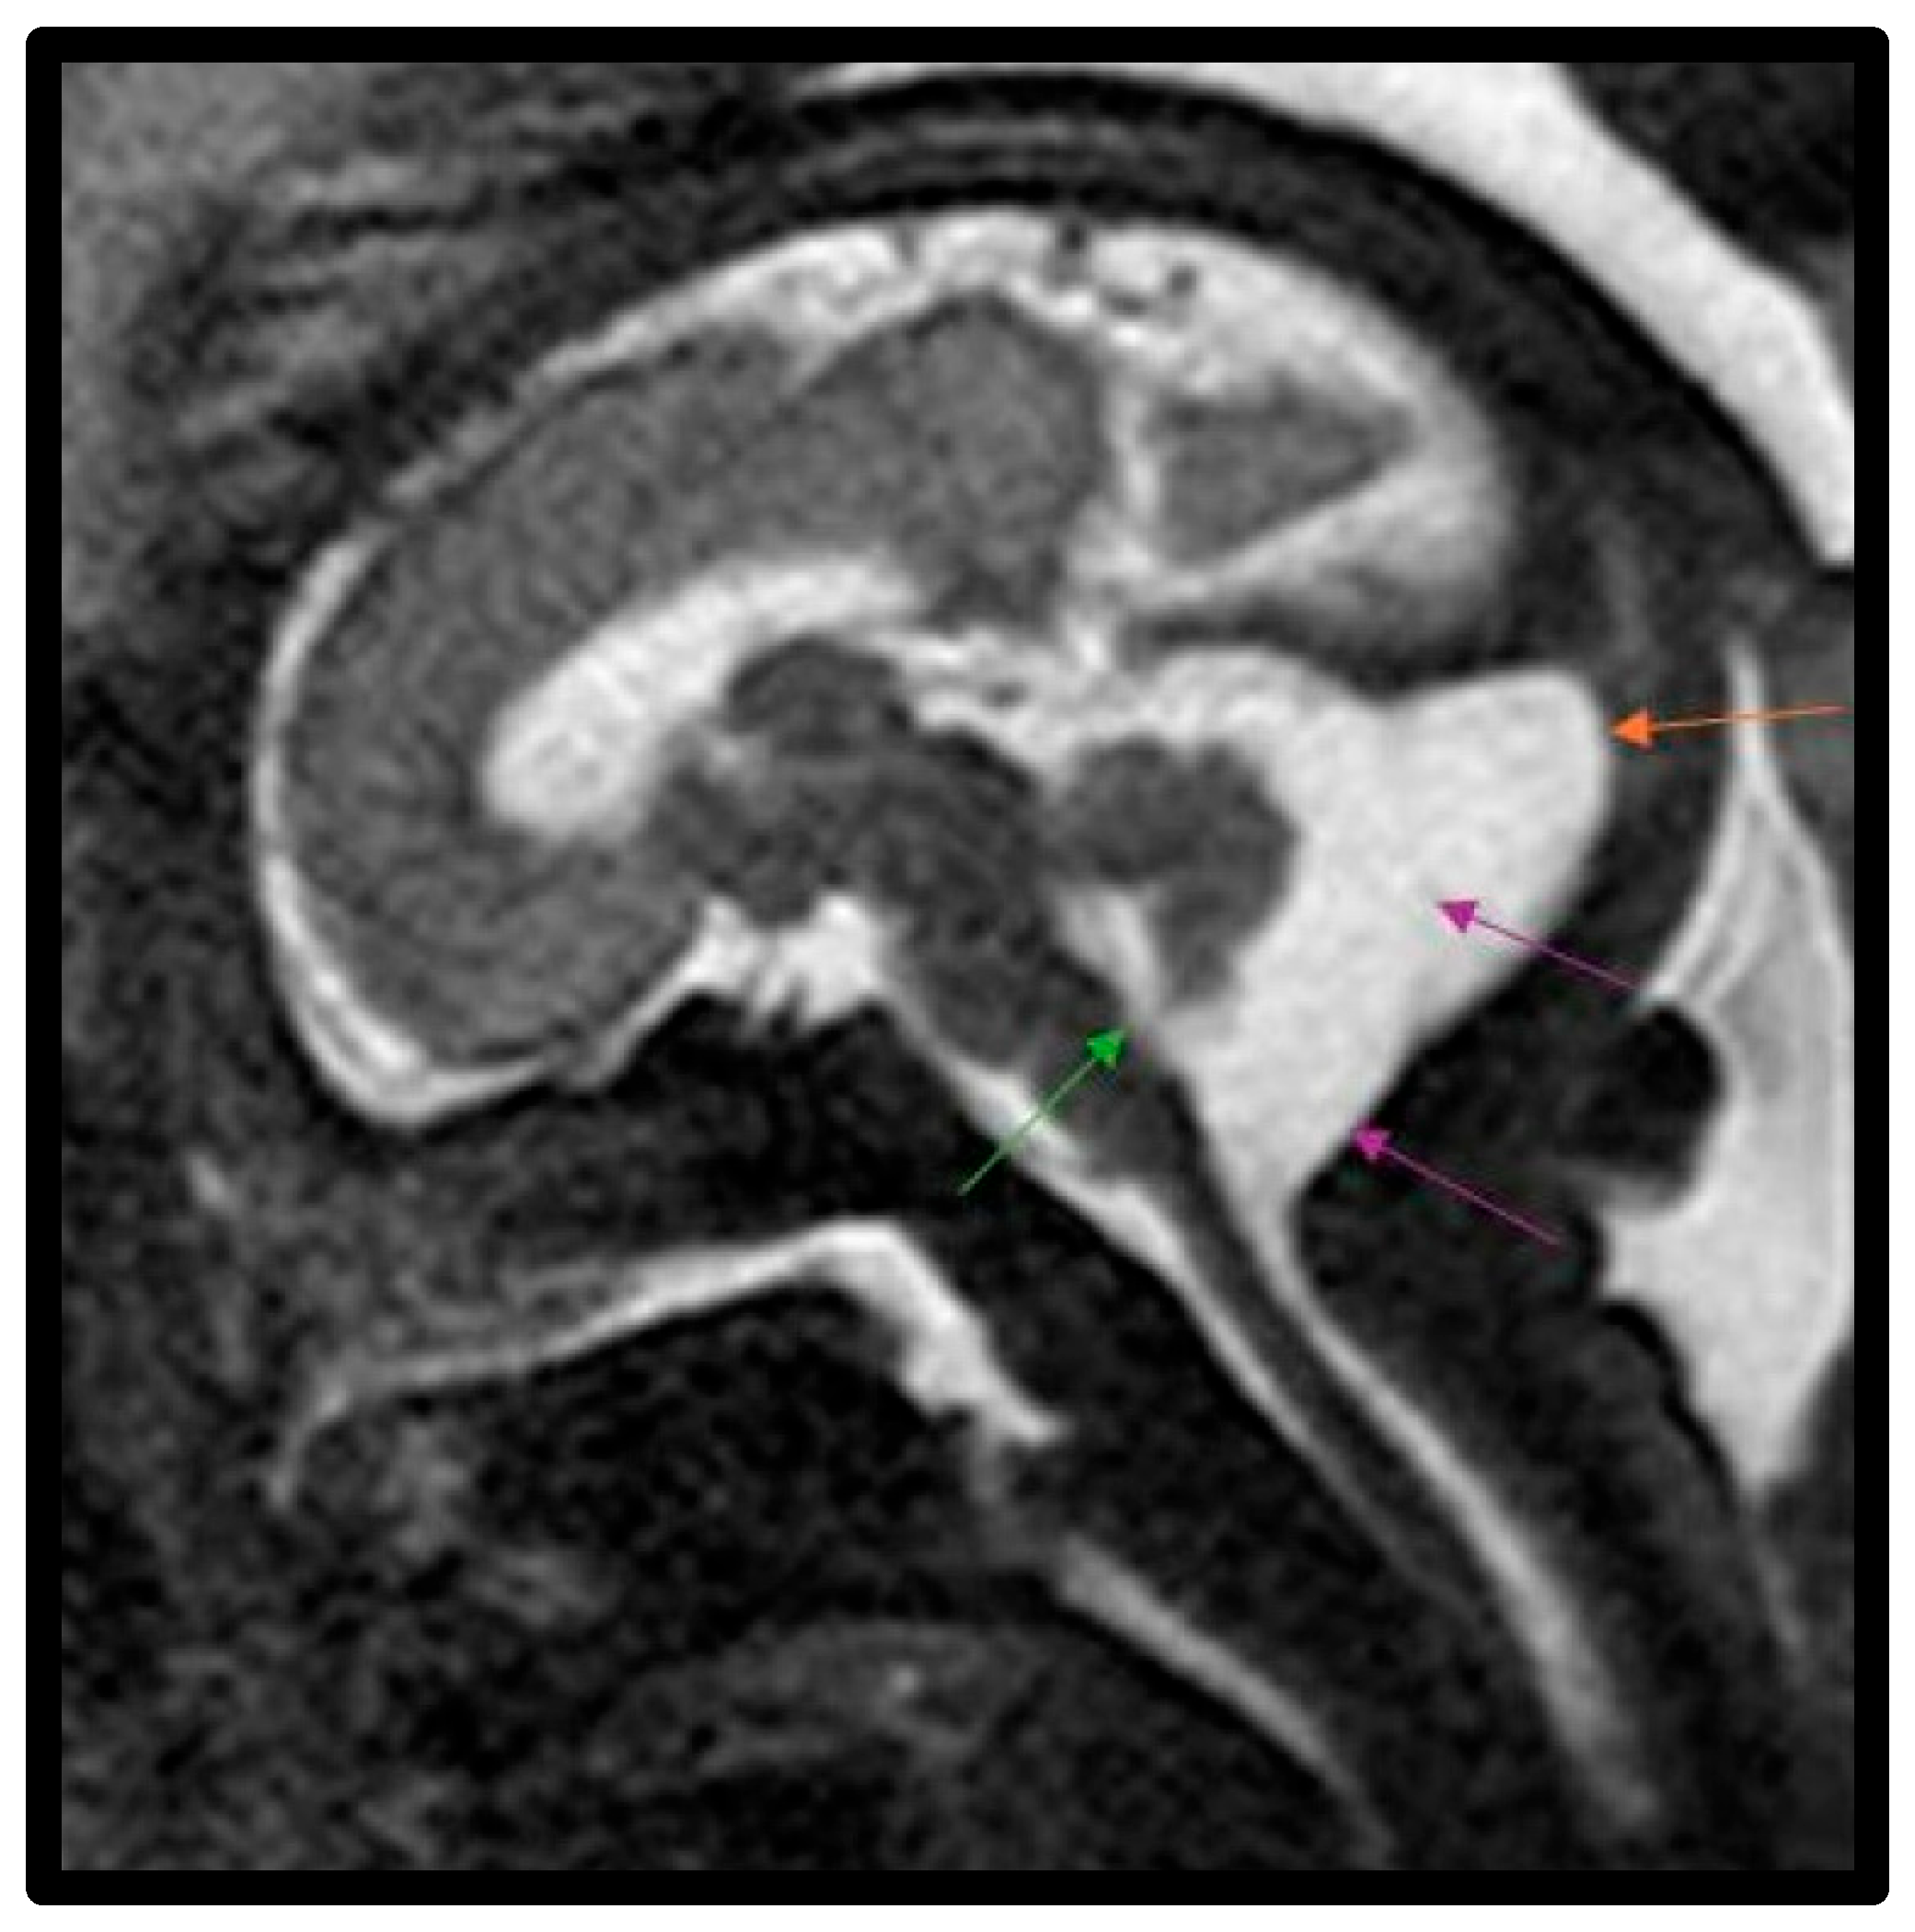

- Bernardo, S.; Vinci, V.; Saldari, M.; Servadei, F.; Silvestri, E.; Giancotti, A.; Aliberti, C.; Porpora, M.G.; Triulzi, F.; Rizzo, G.; et al. Dandy-Walker malformation: Is the ‘tail sign’ the key sign? Prenat. Diagn. 2015, 35, 1358–1364. [Google Scholar] [CrossRef] [PubMed]

- Whitehead, M.T.; Vezina, G.; Schlatterer, S.D.; Mulkey, S.B.; Plessis, A.J. Taenia-tela choroidea complex and choroid plexus location help distinguish Dandy-Walker malformation and Blake pouch cysts. Pediatr. Radiol. 2021, 51, 1457–1470. [Google Scholar] [CrossRef] [PubMed]

- Paladini, D.; Donarini, G.; Parodi, S.; Volpe, G.; Fulcheri, E. Hindbrain morphometry and choroid plexus position in differential diagnosis of posterior fossa cystic malformations. Ultrasound Obstet. Gynecol. 2019, 54, 207–214. [Google Scholar] [CrossRef] [PubMed]

- Murali, L.; Rangasami, R.; Priyanka, C.; Suresh, I.; Suresh, S. Assessment of fastigial angle in fetuses with Blake pouch cyst and vermian hypoplasia on magnetic resonance imaging. J. Pediatr. Neurosci. 2024, 19, 39–44. [Google Scholar] [CrossRef]